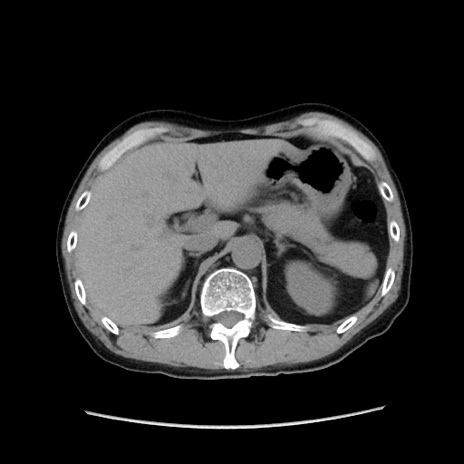

症例37(横断像)

【症例】40歳代 男性

【主訴】腹痛

【現病歴】4時間ほど前に電車に乗車中に臍部上より腹痛出現。徐々に増悪し起立困難となり、救急外来受診。生ものは数日食べていない。今朝お雑煮を食べた。

【身体所見】BT 36.8℃、BP 117/84mmHg、HR 91/min、SpO2 97%、苦悶様、腹部:臍上部広範囲圧痛あり、反跳痛±

【データ】WBC 8100、CRP 0.03